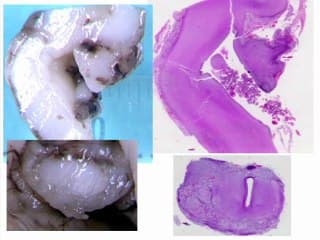

L'auteur nous présente les éléments séméiologiques pour progresser dans les diagnostics des dysraphismes et ainsi approcher leur pronostic. Présentation très claire avec les différentes variétés accessibles au diagnostic : myelomeningocele , moelle attachée basse , lipome du filum etc...